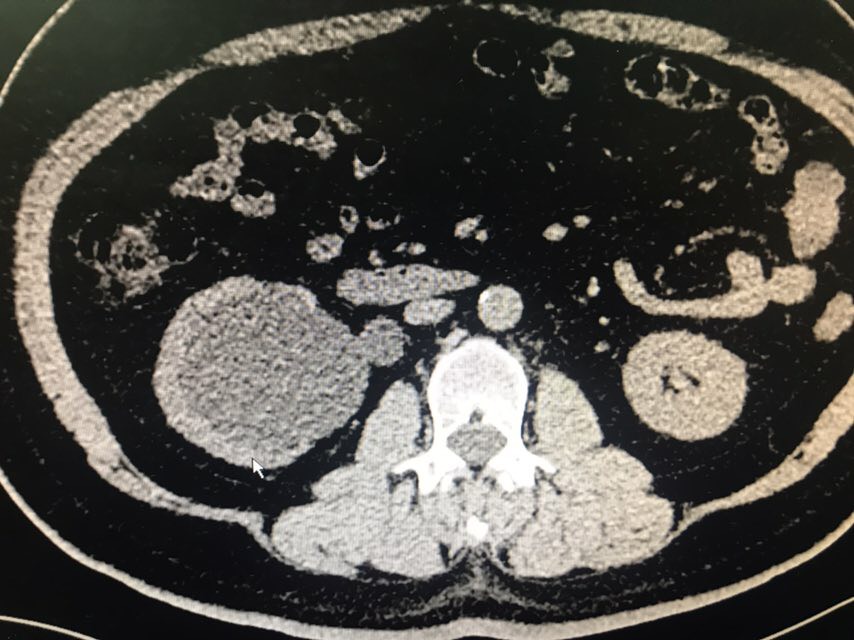

查体:无特殊。辅助检查:全腹CT(我院2018-8-6):右肾盂、肾盏及右输尿管上段明显扩张、积水;右侧输尿管置管。左肾盏区点状结石;双肾囊肿可能。膀胱充盈,壁稍增厚、毛糙,合并炎症可能,胆囊结石。脂肪肝;肝右叶小钙化灶。

从患者CT片子上看,患者右侧输尿管下段狭窄,输尿管支架管返折,因膀胱镜下未能成功取出,故行右侧输尿管探查术。手术顺利,术后给予曲克芦丁脑蛋白水解物注射液5ml治疗,患者术后恢复良好。